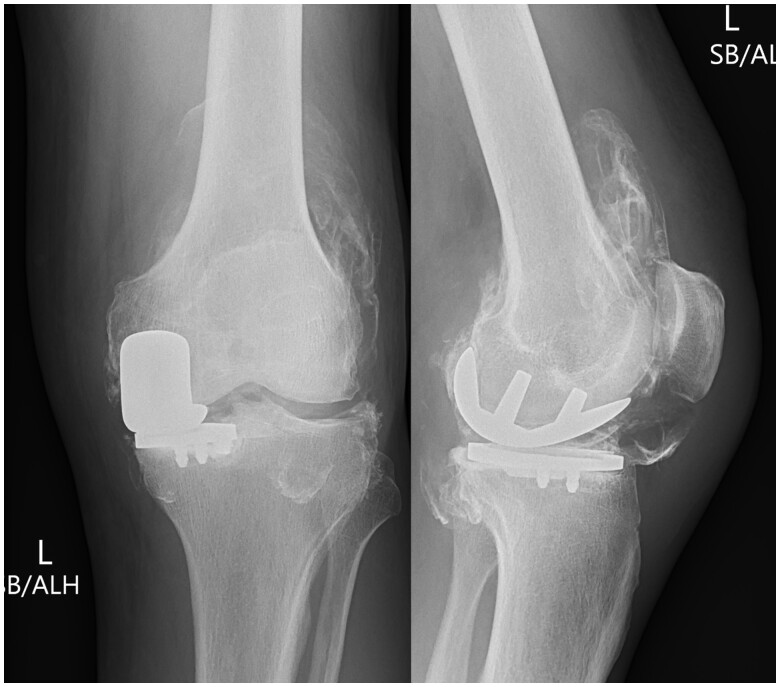

We present the radiological findings in the case of a failed unicompartmental knee arthroplasty (UKA). Although uncommon, these features are highly specific for implant failure and are an indication to consider revision. The aim of this case report is to highlight these characteristic appearances across multiple imaging modalities to both surgeons and radiologists should they encounter this in their practise.

Abstract Image